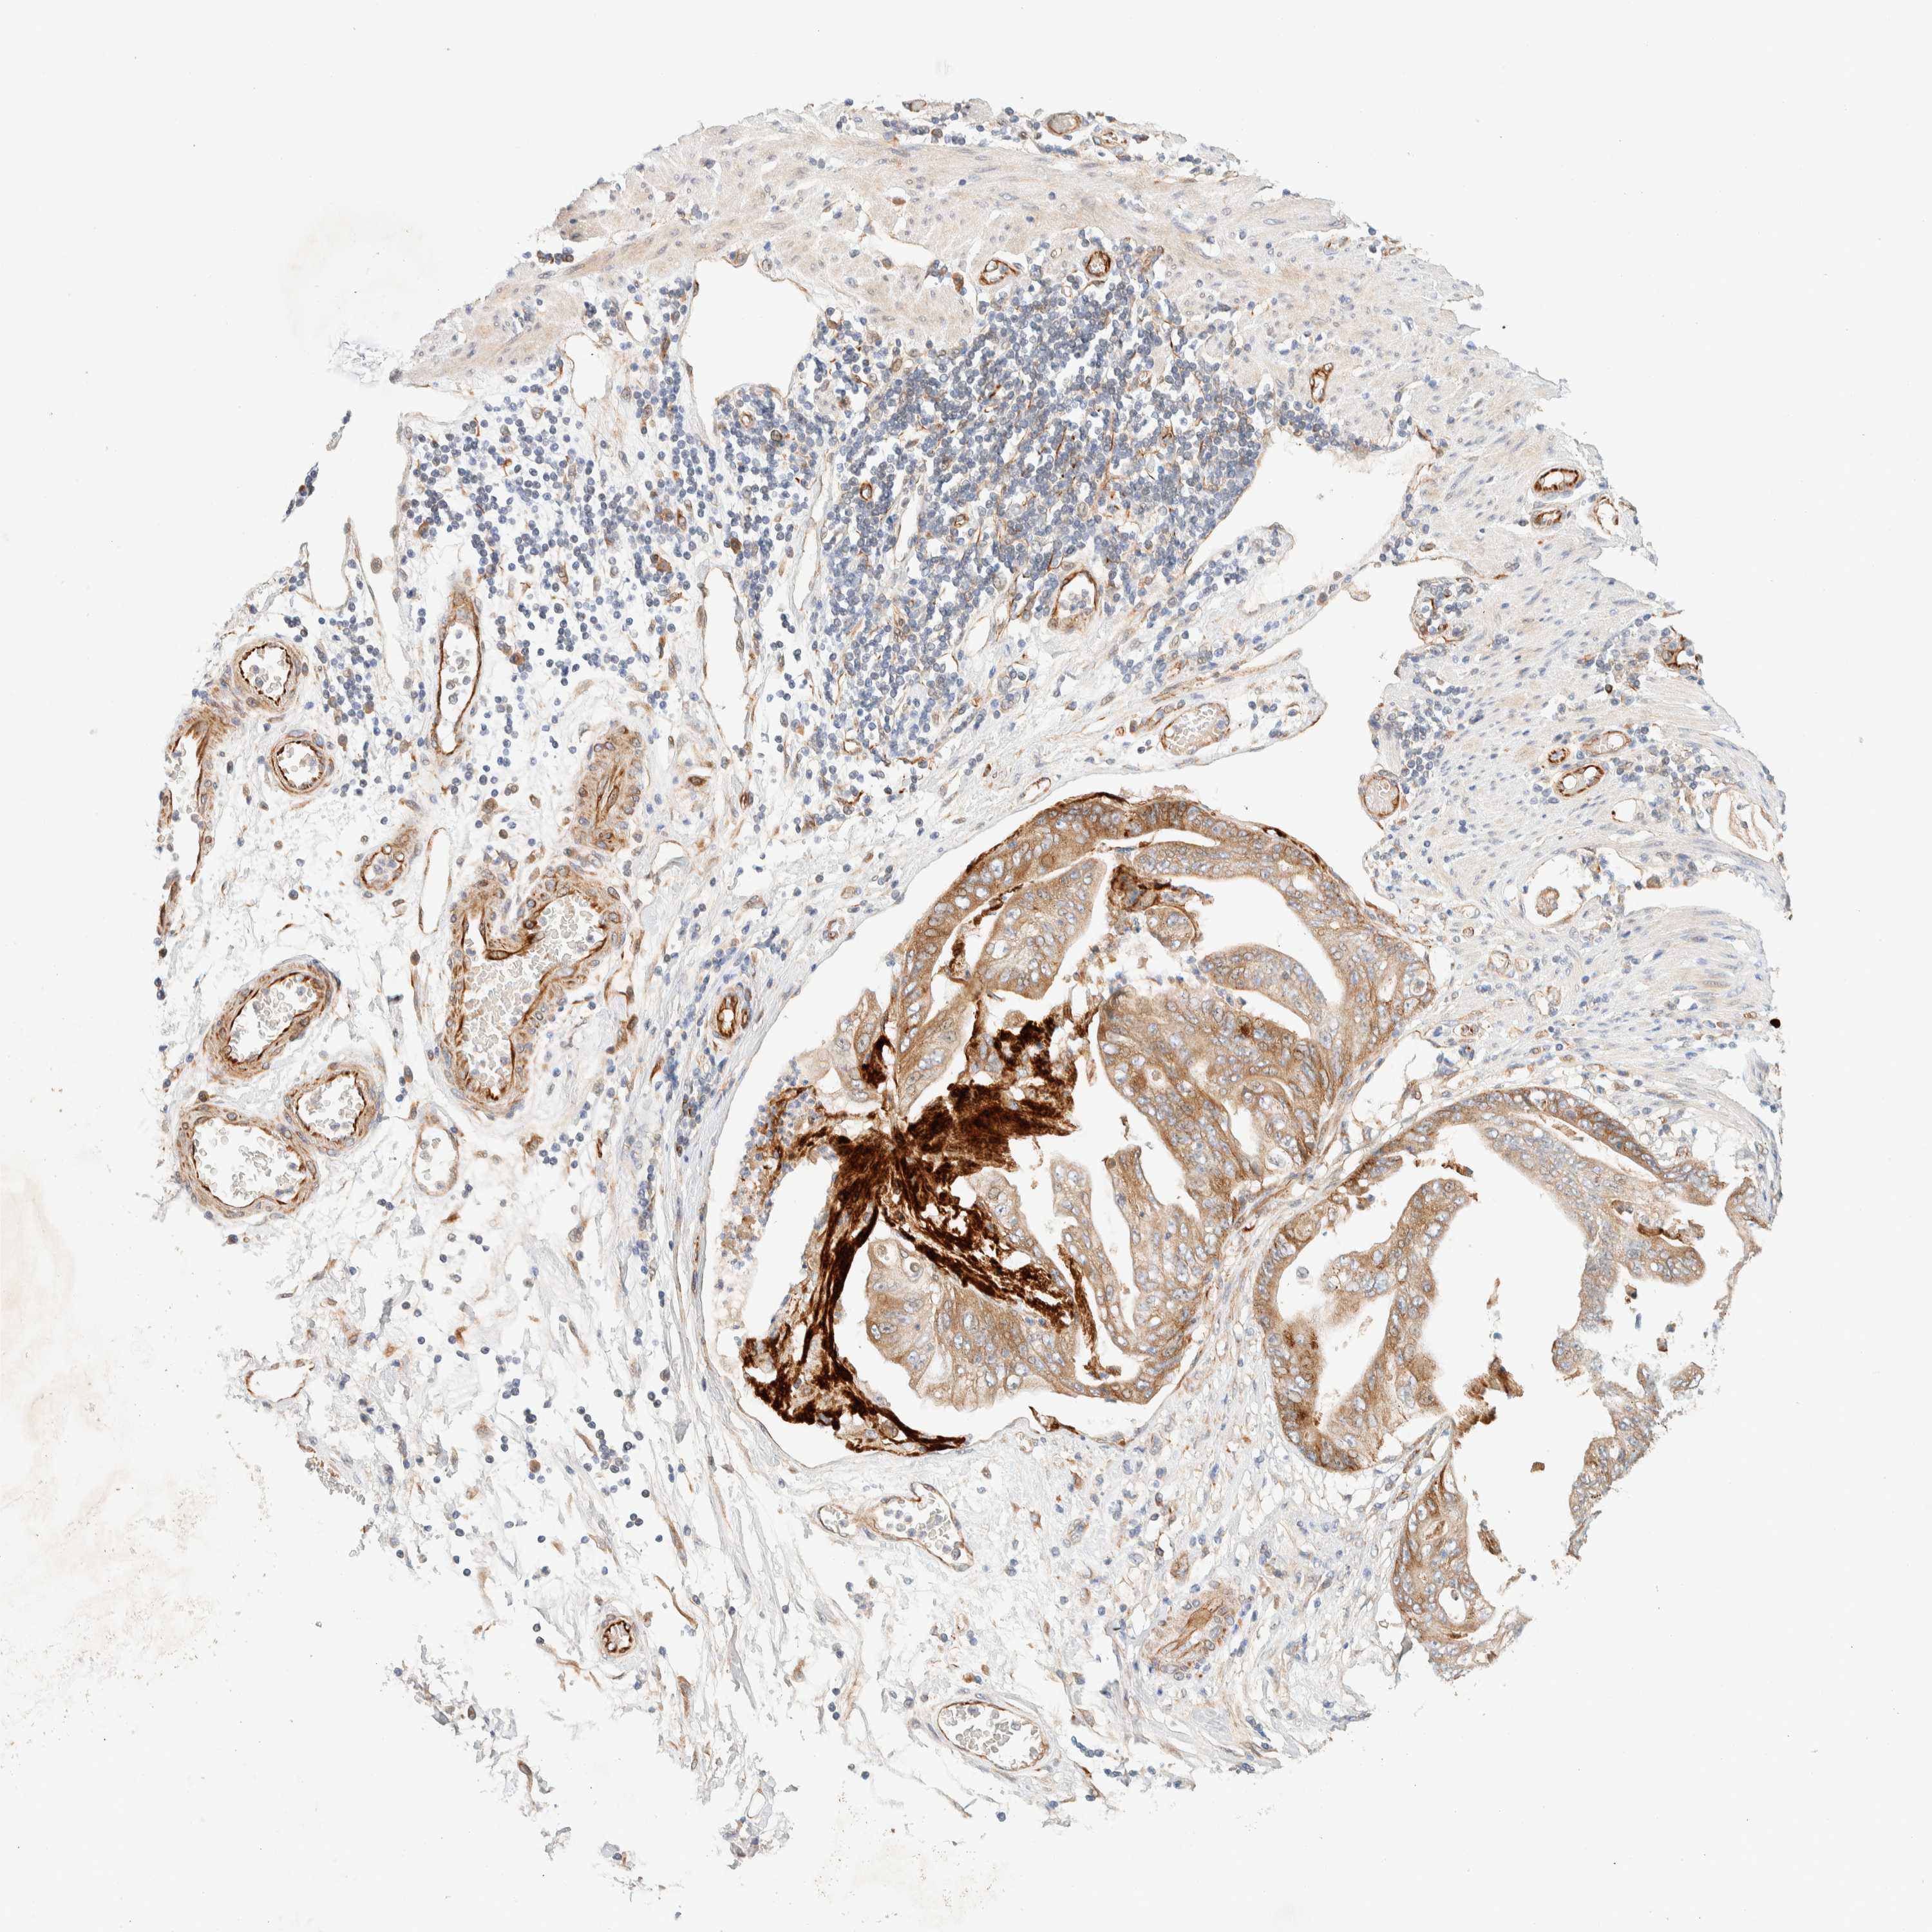

STOMACH CANCER - Protein expressioni

A mouse-over function shows sample information and annotation data. Click on an image to view it in a full screen mode. Samples can be filtered based on level of antibody staining by selecting one or several of the following categories: high, medium, low and not detected. The assay and annotation is described here.

Note that samples used for immunohistochemistry by the Human Protein Atlas do not correspond to samples in the TCGA dataset.

Antibody stainingi

Antibody staining in the annotated cell types in the current human tissue is reported as not detected, low, medium, or high, based on conventional immunohistochemistry profiling in selected tissues. This score is based on the combination of the staining intensity and fraction of stained cells.

Each image is clickable and will lead to virtual microscopy that enables deeper exploration of all samples and also displays staining intensity scores, fraction scores and subcellular localization as well as patient and tissue information for each sample.

Antibody HPA001869

Antibody HPA023882

Staining

High

Medium

Low

Not detected

Intensity

Strong

Moderate

Weak

Negative

Quantity

>75%

75%-25%

<25%

None

Location

Nuclear

Cytoplasmic/membranous

Cytoplasmic/membranous,nuclear

Adenocarcinoma, NOS

Adenocarcinoma, High grade